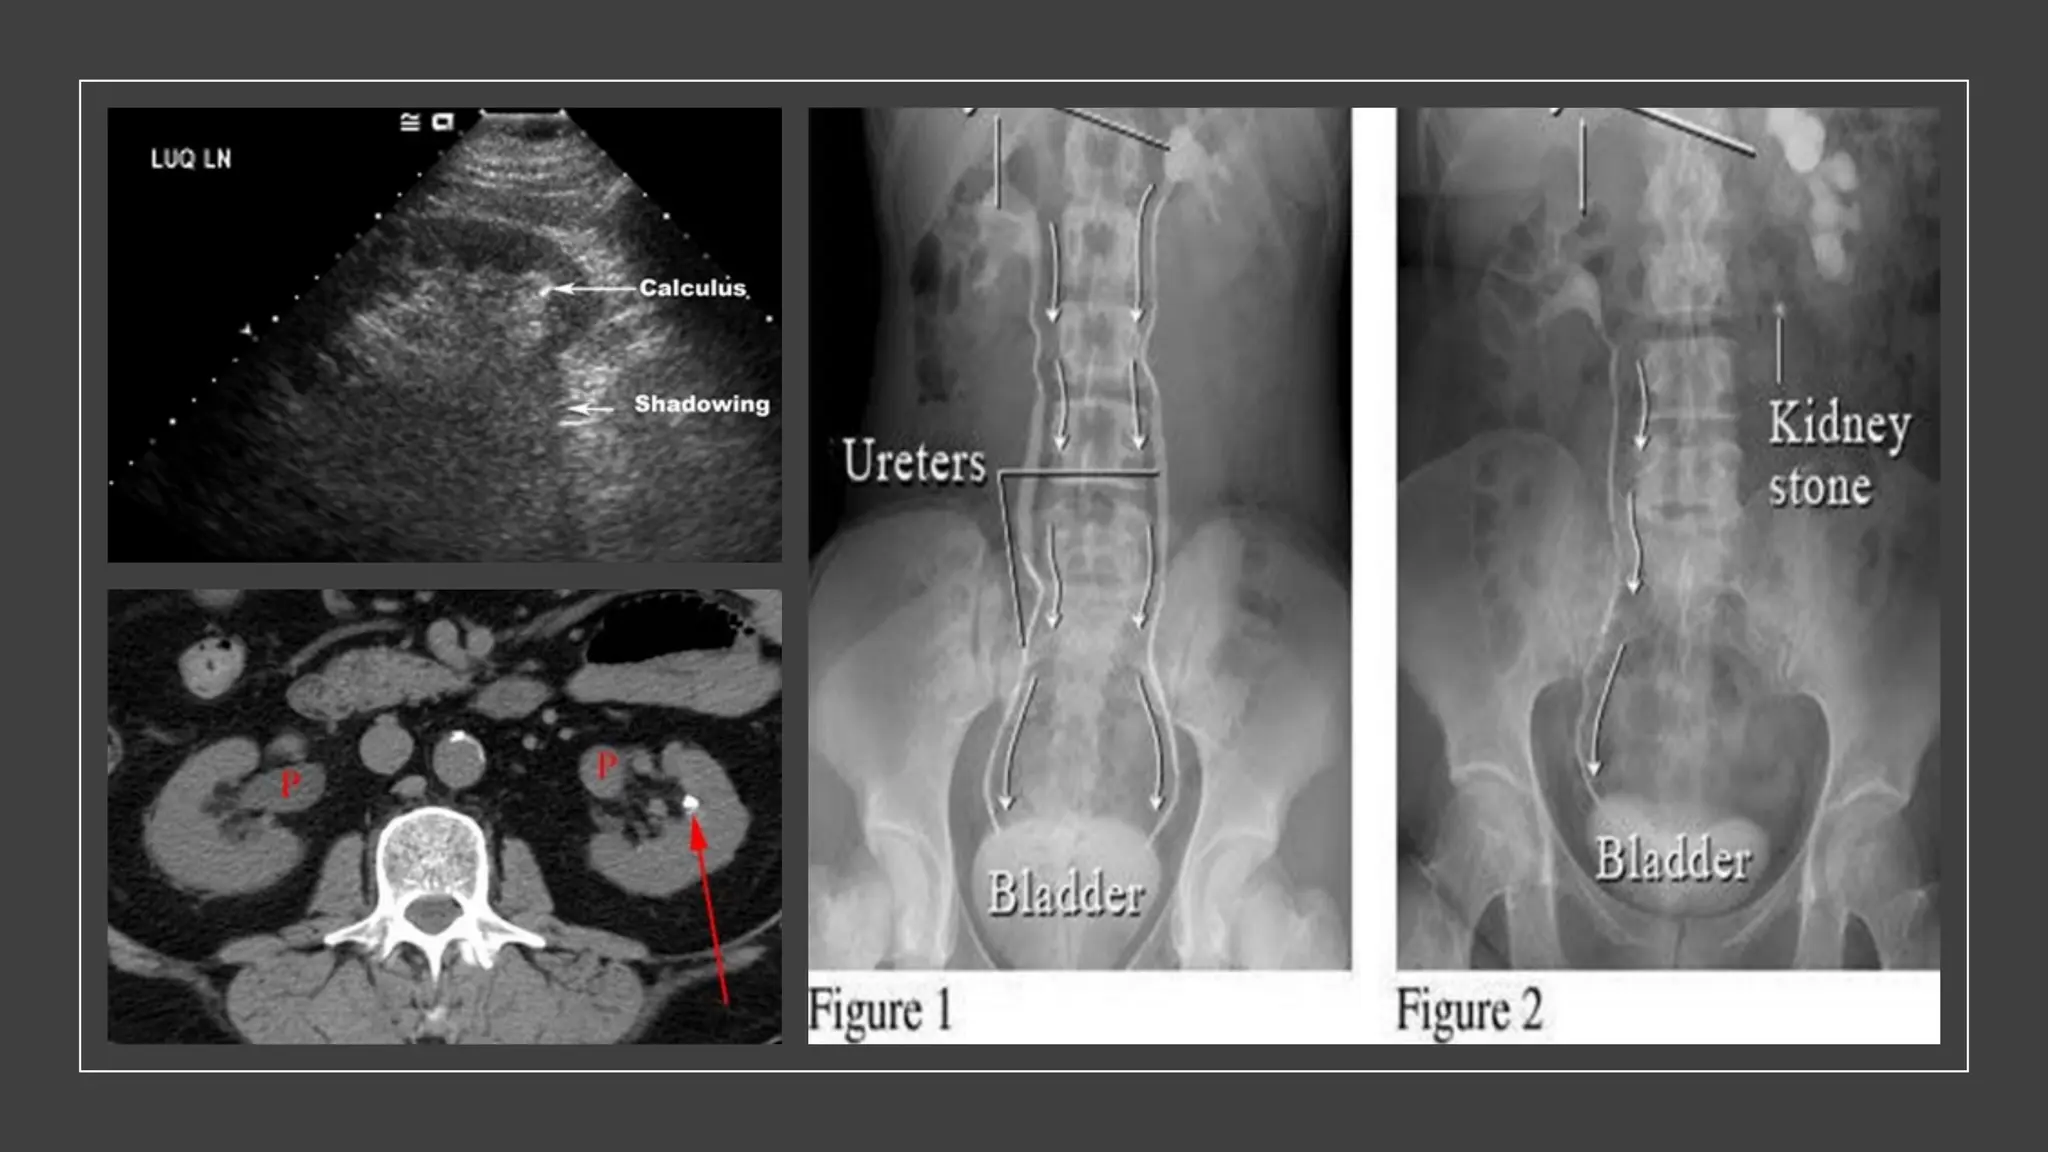

INVESTIGATIONS

• X-ray

• ‘KUB’ film shows kidney, ureter &

bladder

• Diagnose radiopaque stones (mostly

oxalate stone)

• Opacity that maintains its position

relative to the urinary tract is likely to

be calculus

• Ultrasound

• Most value in locating stones for treatment by extracorporeal shock wave lithotripsy

(ESWL)

• Can detect upper hydroureter and hydronephrosis (as complication from stones)